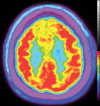

Neurodegenerative diseases are a devastating group of disorders that can be difficult to accurately diagnose. Although these disorders are difficult to manage owing to relatively limited treatment options, an early and correct diagnosis can help with managing symptoms and coping with the later stages of these disease processes. Both anatomic structural imaging and physiologic molecular imaging have evolved to a state in which these neurodegenerative processes can be identified relatively early with high accuracy. To determine the underlying disease, the radiologist should understand the different distributions and pathophysiologic processes involved. High-spatial-resolution MRI allows detection of subtle morphologic changes, as well as potential complications and alternate diagnoses, while molecular imaging allows visualization of altered function or abnormal increased or decreased concentration of disease-specific markers. These methodologies are complementary. Appropriate workup and interpretation of diagnostic studies require an integrated, multimodality, multidisciplinary approach. This article reviews the protocols and findings at MRI and nuclear medicine imaging, including with the use of flurodeoxyglucose, amyloid tracers, and dopaminergic transporter imaging (ioflupane). The pathophysiology of some of the major neurodegenerative processes and their clinical presentations are also reviewed; this information is critical to understand how these imaging modalities work, and it aids in the integration of clinical data to help synthesize a final diagnosis. Radiologists and nuclear medicine physicians aiming to include the evaluation of neurodegenerative diseases in their practice should be aware of and familiar with the multiple imaging modalities available and how using these modalities is essential in the multidisciplinary management of patients with neurodegenerative diseases.©RSNA, 2020.